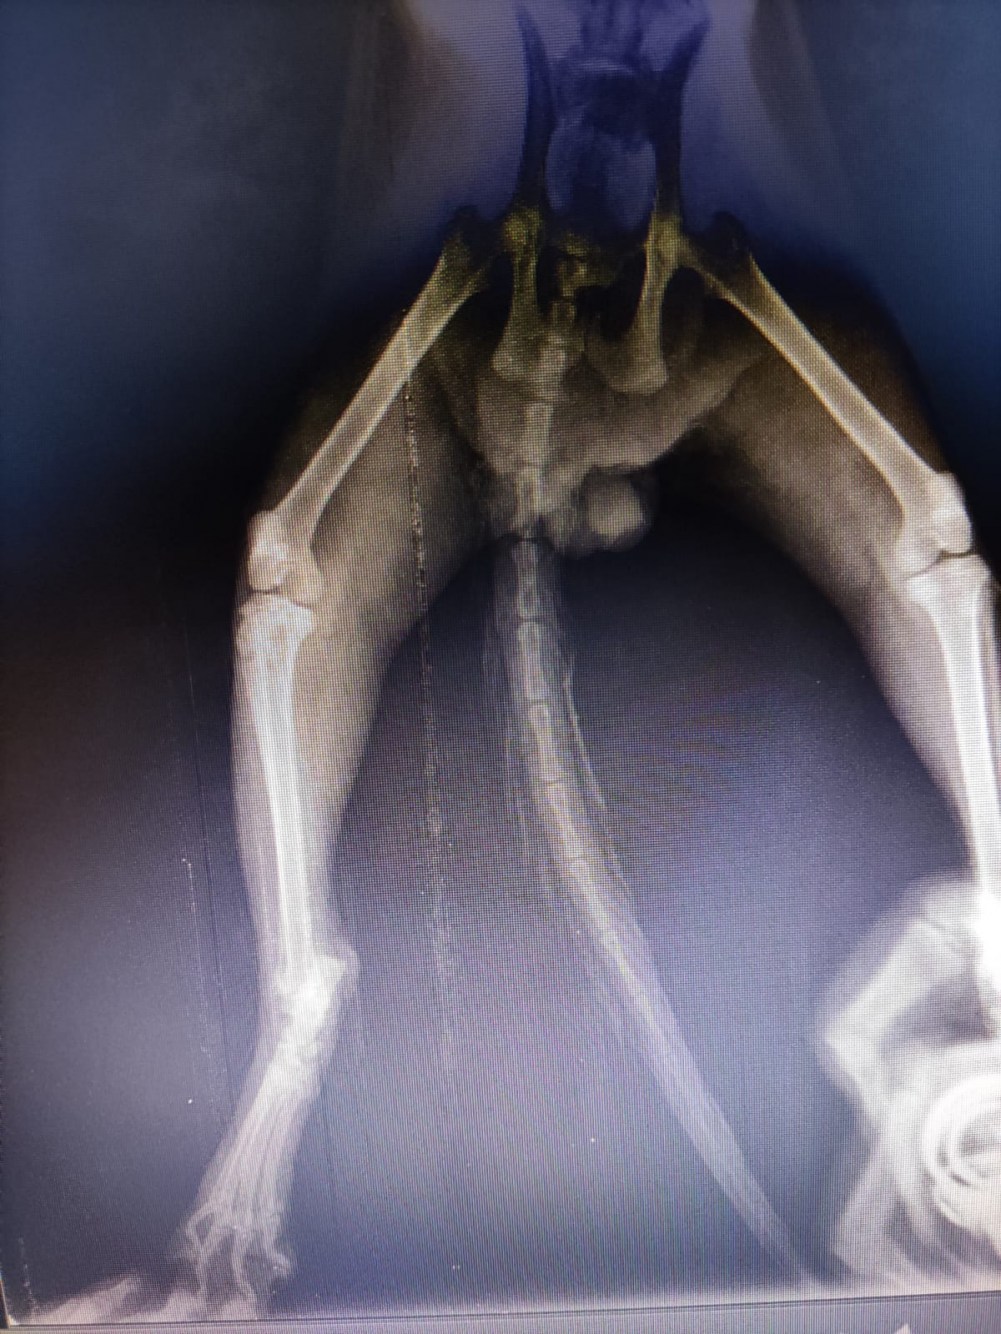

Veteriner kliniğinde yapılan muayenede BONCUK’un omuriliğinde ve arkada sağ ayağında kırık olduğu tespit edildi. Ayrıca kedinin Rektum’unda ve bağırsaklarında 4-5 santimlik genişleme olduğu, bu oluşumun kedinin tecavüze uğraması sonrası oluştuğu belirlendi.

Kedinin ilk müdahalesini yapan veteriner hekim Neslihan Yazıcı “Akşam saat 18.00 sularında hayvan sever olan hanımefendi sokakta bulduğu ve yürüyemiyor şikayeti ile kediyi kliniğimize getirdi. İlk etaptaki muayenesinde rektum bölgesinde ki 4-5 santimetrelik açıklık dikkatimizi çekti. Daha sonrasında yaz mevsiminde olduğumuz için kurtlanma durumu vardı. İlk muayenede kurtlar temizlendi. Rektum boşaltıldı. Daha sonrasında röntgen çektiğimizde omurga kırığı ve bacakta kırık olduğunu tespit ettik. Rektum da ki bu kadar büyük bir açıklık maalesef ne trafik kazası, ne şiddetten kaynaklı olmayıp direk olarak tecavüz vakası olduğunu belirttik. İlk muayeneler bu şekilde” dedi.